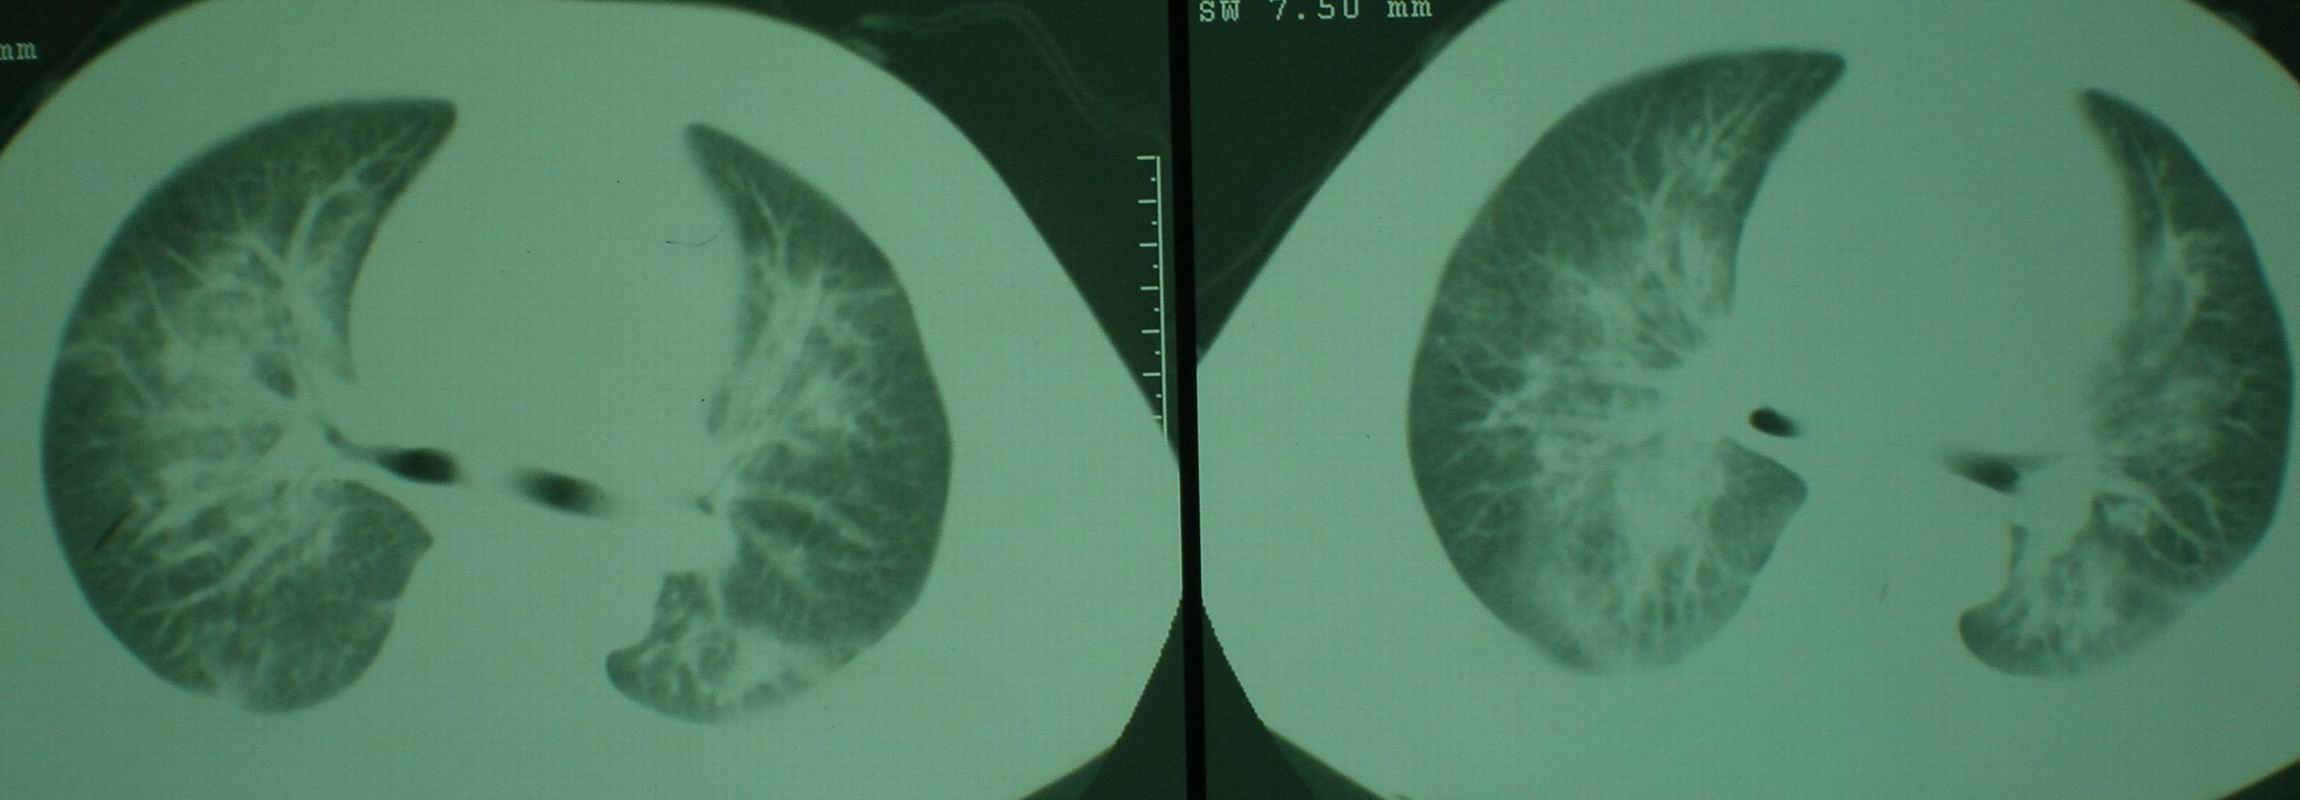

2008年11月18日今天的ct片

2008年9月18日ct片

2008年9月8日ct片:

[face=宋体]显然上级医院进行了抗结核,抗真菌,抗炎等治疗,目前病人肺内病灶基本消失,双侧胸腔积液,右侧积液量有吸收,抗结核一个多月,现在病人疑问,结核的诊断是否有疑义,抗结核是否继续,因为那个毕竟副作用大。[/face]

我仔细看了下病人的出院小结,当时情况危急,诊断里有1型呼衰。心包周围的是脂肪密度。结合三次ct扫描的图象分析,个人认为:1、病人目前肺部病灶基本消失,双侧胸腔内少量积液,抗结核治疗才一个多月,就算是结核,抗结核治疗有效果,为何效果如此好,一点纤维灶的痕迹都没有呢,再就是患者做过气管镜检查及活检、痰检均未找到结核的证据。所以不支持结核的诊断。

2、结合现在的ct片,考虑:肺水肿及真菌感染,双侧胸腔积液。